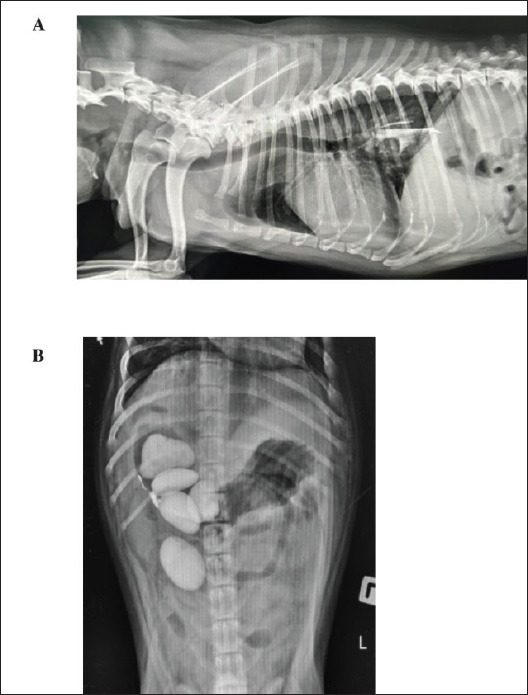

目的:本研究旨在识别、分类和比较狗的胃肠道异物,特别关注那些引起阻塞的异物。该研究还试图区分食道和胃中的异物,包括骨头、塑料袋、水果种子、石头和金属丝等物质的类型。方法:对261只犬(公151只,母110只)的食管或胃异物(n = 111)进行回顾性研究。样本包括188只小型犬(24公斤)。结果:胃异物(57.47%)高于食管异物(42.53%)。食道病例以小型犬为主(92.79%),中型犬占很小比例(7.21%)。胃病例中,小型犬数量较多(56.67%),中型犬(22.00%)和大型犬(21.33%)比例显著。小型犬更容易在食道中发现异物,而大型犬(中型和大型犬)更容易在胃中发现异物(p < 0.001)。食道和胃之间出现了明显的物质形态。值得注意的是,食管(61.26%)和干狗零食(23.42%)的发生率高于胃(分别为2.67%和0.00%)。相反,胃中织物(20.00%比1.80%)、植物材料(18.67%比4.50%)、金属物体(18.00%比8.11%)、岩石(12.67%比0.9%)、橡胶材料(10.67%比0.00%)、塑料材料(6.67%比0.00%)和毛球(2.67%比0.00%)的发生率分别较高。时间分析显示,在食管内,28.83%的病例在24 h内取出异物,56.76%的病例在2-7天内取出,14.41%的病例在7天以上取出异物。对于胃内异物,23.33%在24小时内取出,30.00%在2 ~ 7天内取出,22.00%在7天以上取出,24.67%时间不详。其中,食管异物111例,胃异物150例。主要采用内镜方法清除异物,4例(3.60%)食管和8例(5.30%)胃需要手术,包括不可破碎的骨头和橡皮鸭等耐药物品。在完全随访的犬中,手术切除食管异物的死亡率(3/4,75.00%)高于内镜切除(3/56,5.36%)(p < 0.002),而手术或内镜切除胃异物的犬无死亡(p = 0.149)。结论:食管异物主要由骨头和狗干零食组成,胃异物多由织物、植物材料和金属物体组成。这些组成上的差异突出了针对具体地点的管理策略的必要性。

Results: The study's findings indicate a higher prevalence of gastric foreign bodies (57.47%) compared to esophageal foreign bodies (42.53%). Small breeds dominated esophageal cases (92.79%), with only a small percentage being medium breeds (7.21%). In contrast, gastric cases included a high number of small breeds (56.67%), as well as significant percentages of medium (22.00%) and large breeds (21.33%). Small-breed dogs were more likely to have foreign bodies in the esophagus, while larger dogs (medium and large breeds) were more likely to have them in the stomach (p < 0.001). Distinct material patterns emerged between the esophagus and stomach. Notably, the esophagus showed a higher incidence of bones (61.26%) and dried dog snacks (23.42%) compared to the stomach (2.67% and 0.00%, respectively). Conversely, the stomach exhibited a higher incidence of fabrics (20.00% vs. 1.80%), plant materials (18.67% vs. 4.50%), metallic objects (18.00% vs. 8.11%), rocks (12.67% vs. 0.9%), rubber materials (10.67% vs. 0.00%), plastic materials (6.67% vs. 0.00%), and hairballs (2.67% vs. 0.00%), respectively. A temporal analysis revealed that within the esophagus, 28.83% of cases underwent foreign body removal within 24 h, 56.76% within 2-7 days, and 14.41% after more than 7 days. For foreign bodies within the stomach, removal occurred in 23.33% of cases within 24 h, 30.00% within 2 to 7 days, 22.00% after more than 7 days, and 24.67% at an unknown timing. A total of 111 cases involved foreign bodies lodged in the esophagus, and 150 cases involved items stuck in the stomach. Endoscopic methods were primarily employed to remove foreign bodies, with surgical intervention required for 4 (3.60%) esophageal and 8 (5.30%) gastric cases, including noncrushable bones and resistant items such as rubber ducks. In dogs with complete follow-up, surgical removal of esophageal foreign bodies had a higher mortality rate (3/4, 75.00%) compared with endoscopic removal (3/56, 5.36%) (p < 0.002), while no mortality was observed in dogs with gastric foreign bodies undergoing surgical or endoscopic removal (p = 0.149).